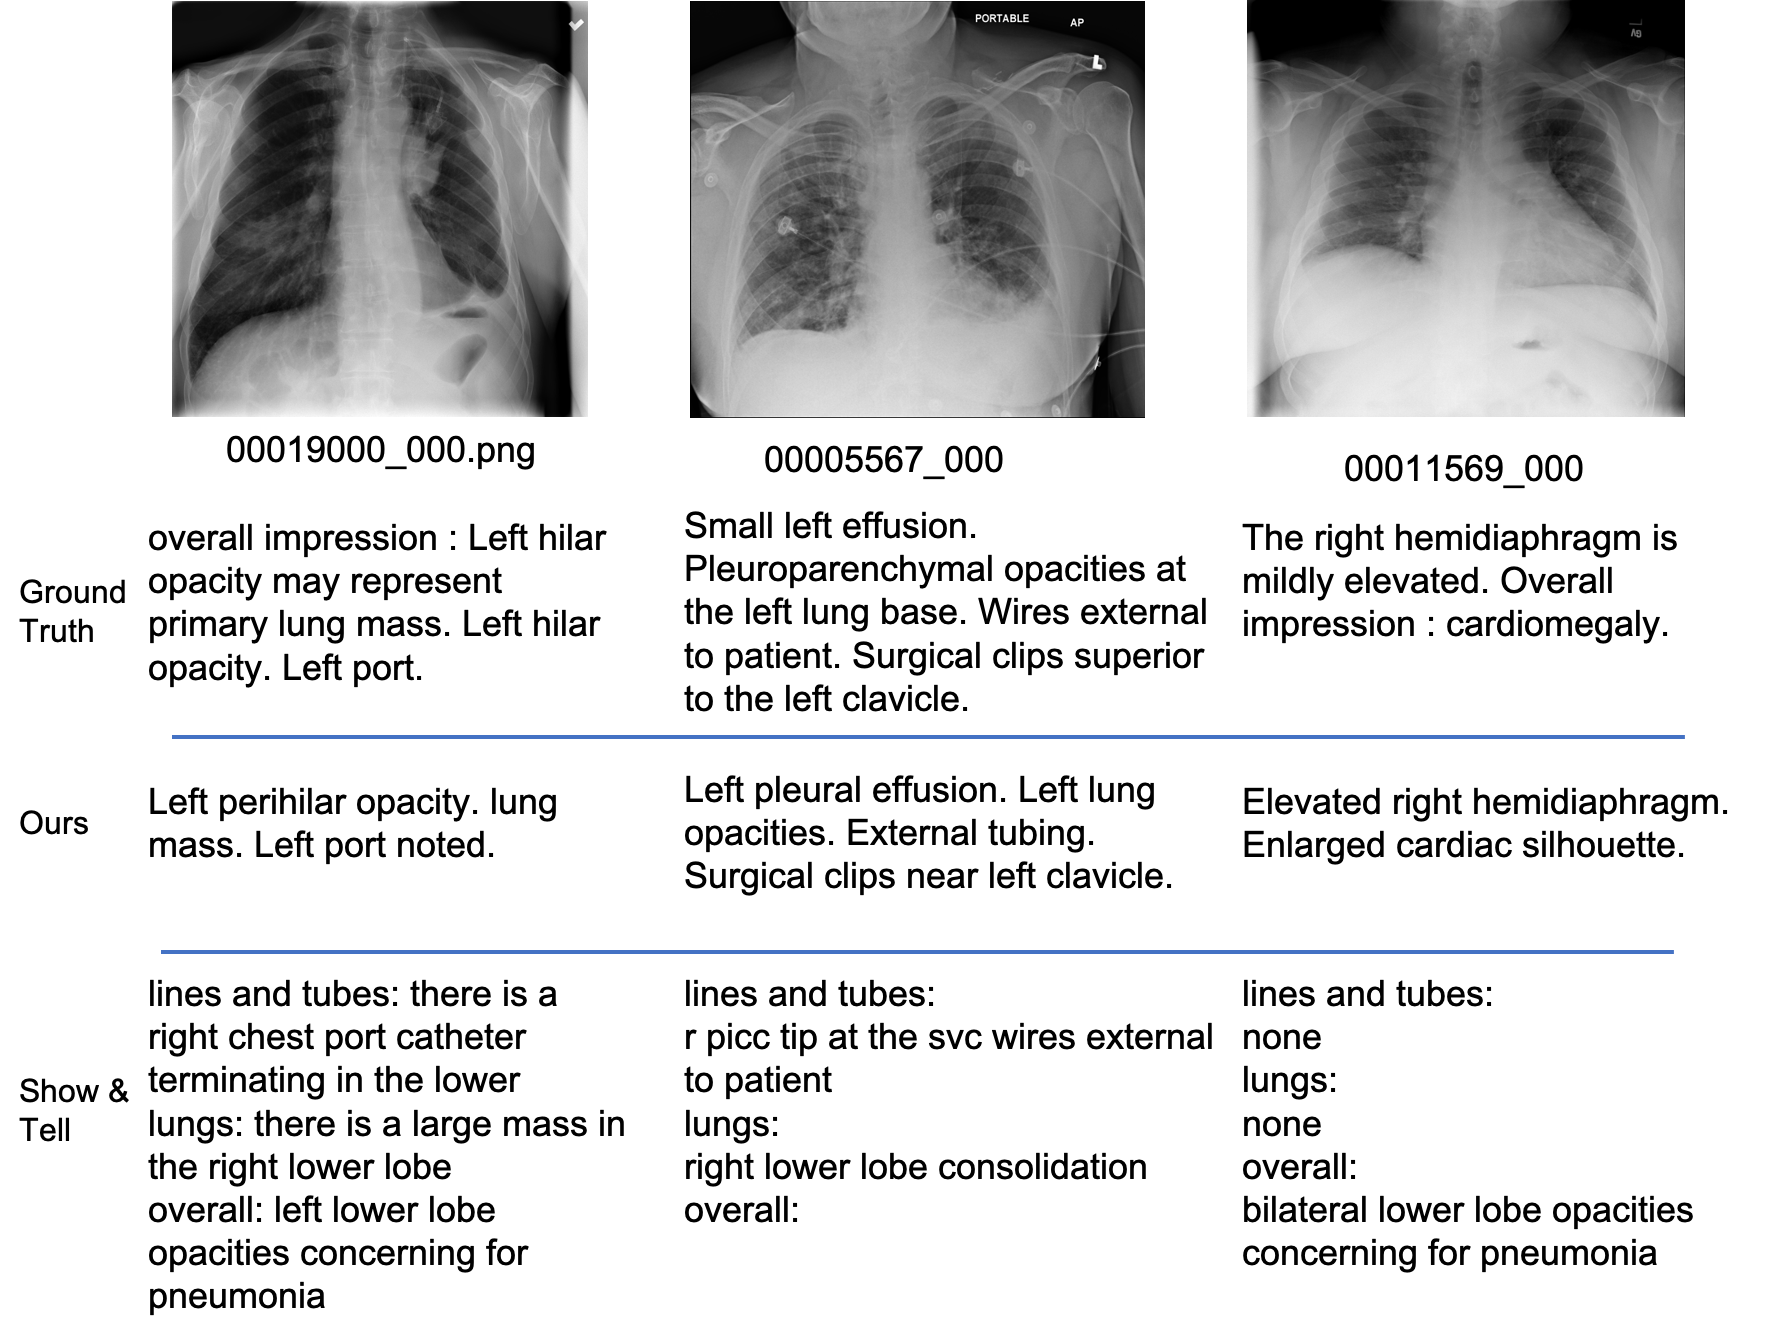

Figure 4: Illustration of quality of reports generated by different methods.

Evaluation of report generation: Due to the ontological mapping used to abstract the description of findings, the match produced from our approach is at a more semantic level rather than lexical in comparison to other approaches. Figure 4 shows the reports manually and automatically produced by our approach and a comparative approach implemented from a visual attention-based captioning model [21]. We compared the performance of our algorithm with several state-of-the-art baselines from recent literature [21, 26, 13, 16, 10, 29]. These included a range of approaches from visual attention-based captioning [21], knowledge-driven report generation [13], clinically accurate report generation [16], to a strawman approach using a set of template sentences manually chosen by clinicians for the FFL labels instead of the nearest report selection algorithm described earlier. Although we have tested our algorithm for very large number of images from the combined MIMIC-NIH data, for purposes of comparison, we show the results on the same Indiana test dataset that has been used most commonly by other algorithms as reported in [10]. The resulting performance using the popular scoring metrics is shown in Table 3 showing that our algorithm outperforms other approaches in all the established scoring metrics.